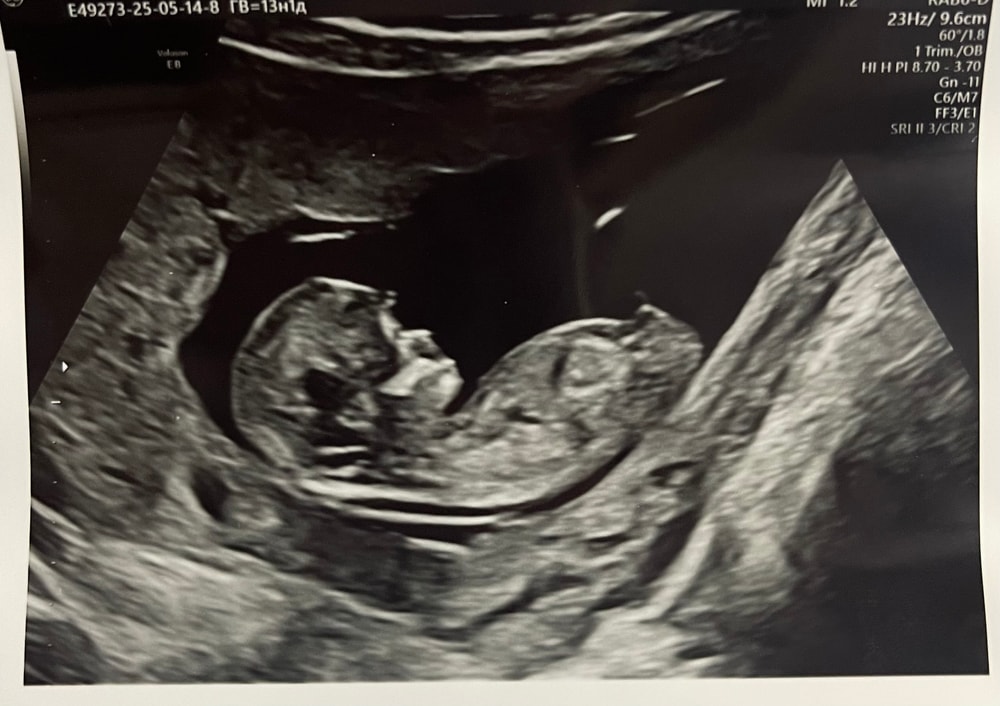

Пол малышаДевочки кто опытный в определении? Пойду через 4 дня уже 15 будет, узи экспертного класса будет и узист сказал уже точно определим на сроке таком. На скрининге доктор сказал не понятно кто было 12,5 по ктр. Но доктор не разговорчивый совсем был от жк направили😅

Похоже на мальчика